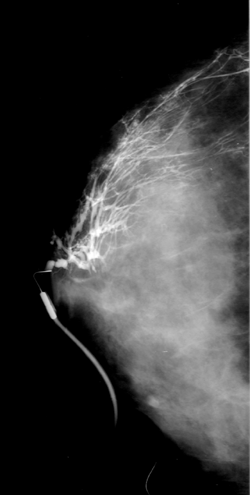

mammopositie mammofoto

Mammografie

Hier wordt met behulp van een speciaal voor dit onderzoek ontworpen toestel foto's gemaakt van het borstweefsel. Hierbij wordt de borst samengedrukt om de weefsels beter in beeld te krijgen alsook om de stralingsbelasting zo laag mogelijk te houden.